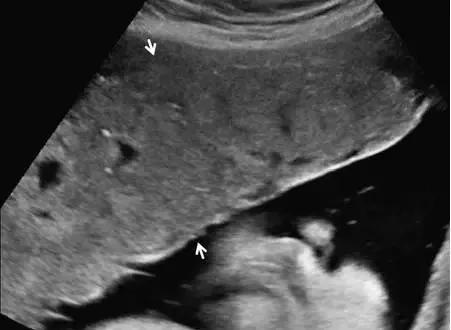

巨胎盘极易并发胎盘发育不全。形似凝胶样的厚胎盘可随着母体腹腔压力而轻微颤抖,其并发胎儿宫内发育受限的风险可达 60%~75%。产前超声发现胎盘增厚时,应详细检查胎儿。胎盘下肌瘤、胎盘早剥以及当胎盘后血肿与胎盘的回声相一致时,可误诊为胎盘增厚(图 7)。

图 7 示孕 34 周时的巨胎盘,箭头示胎盘横切面,厚度为 6 cm,该孕妇系糖尿病患者,胎儿为巨大儿